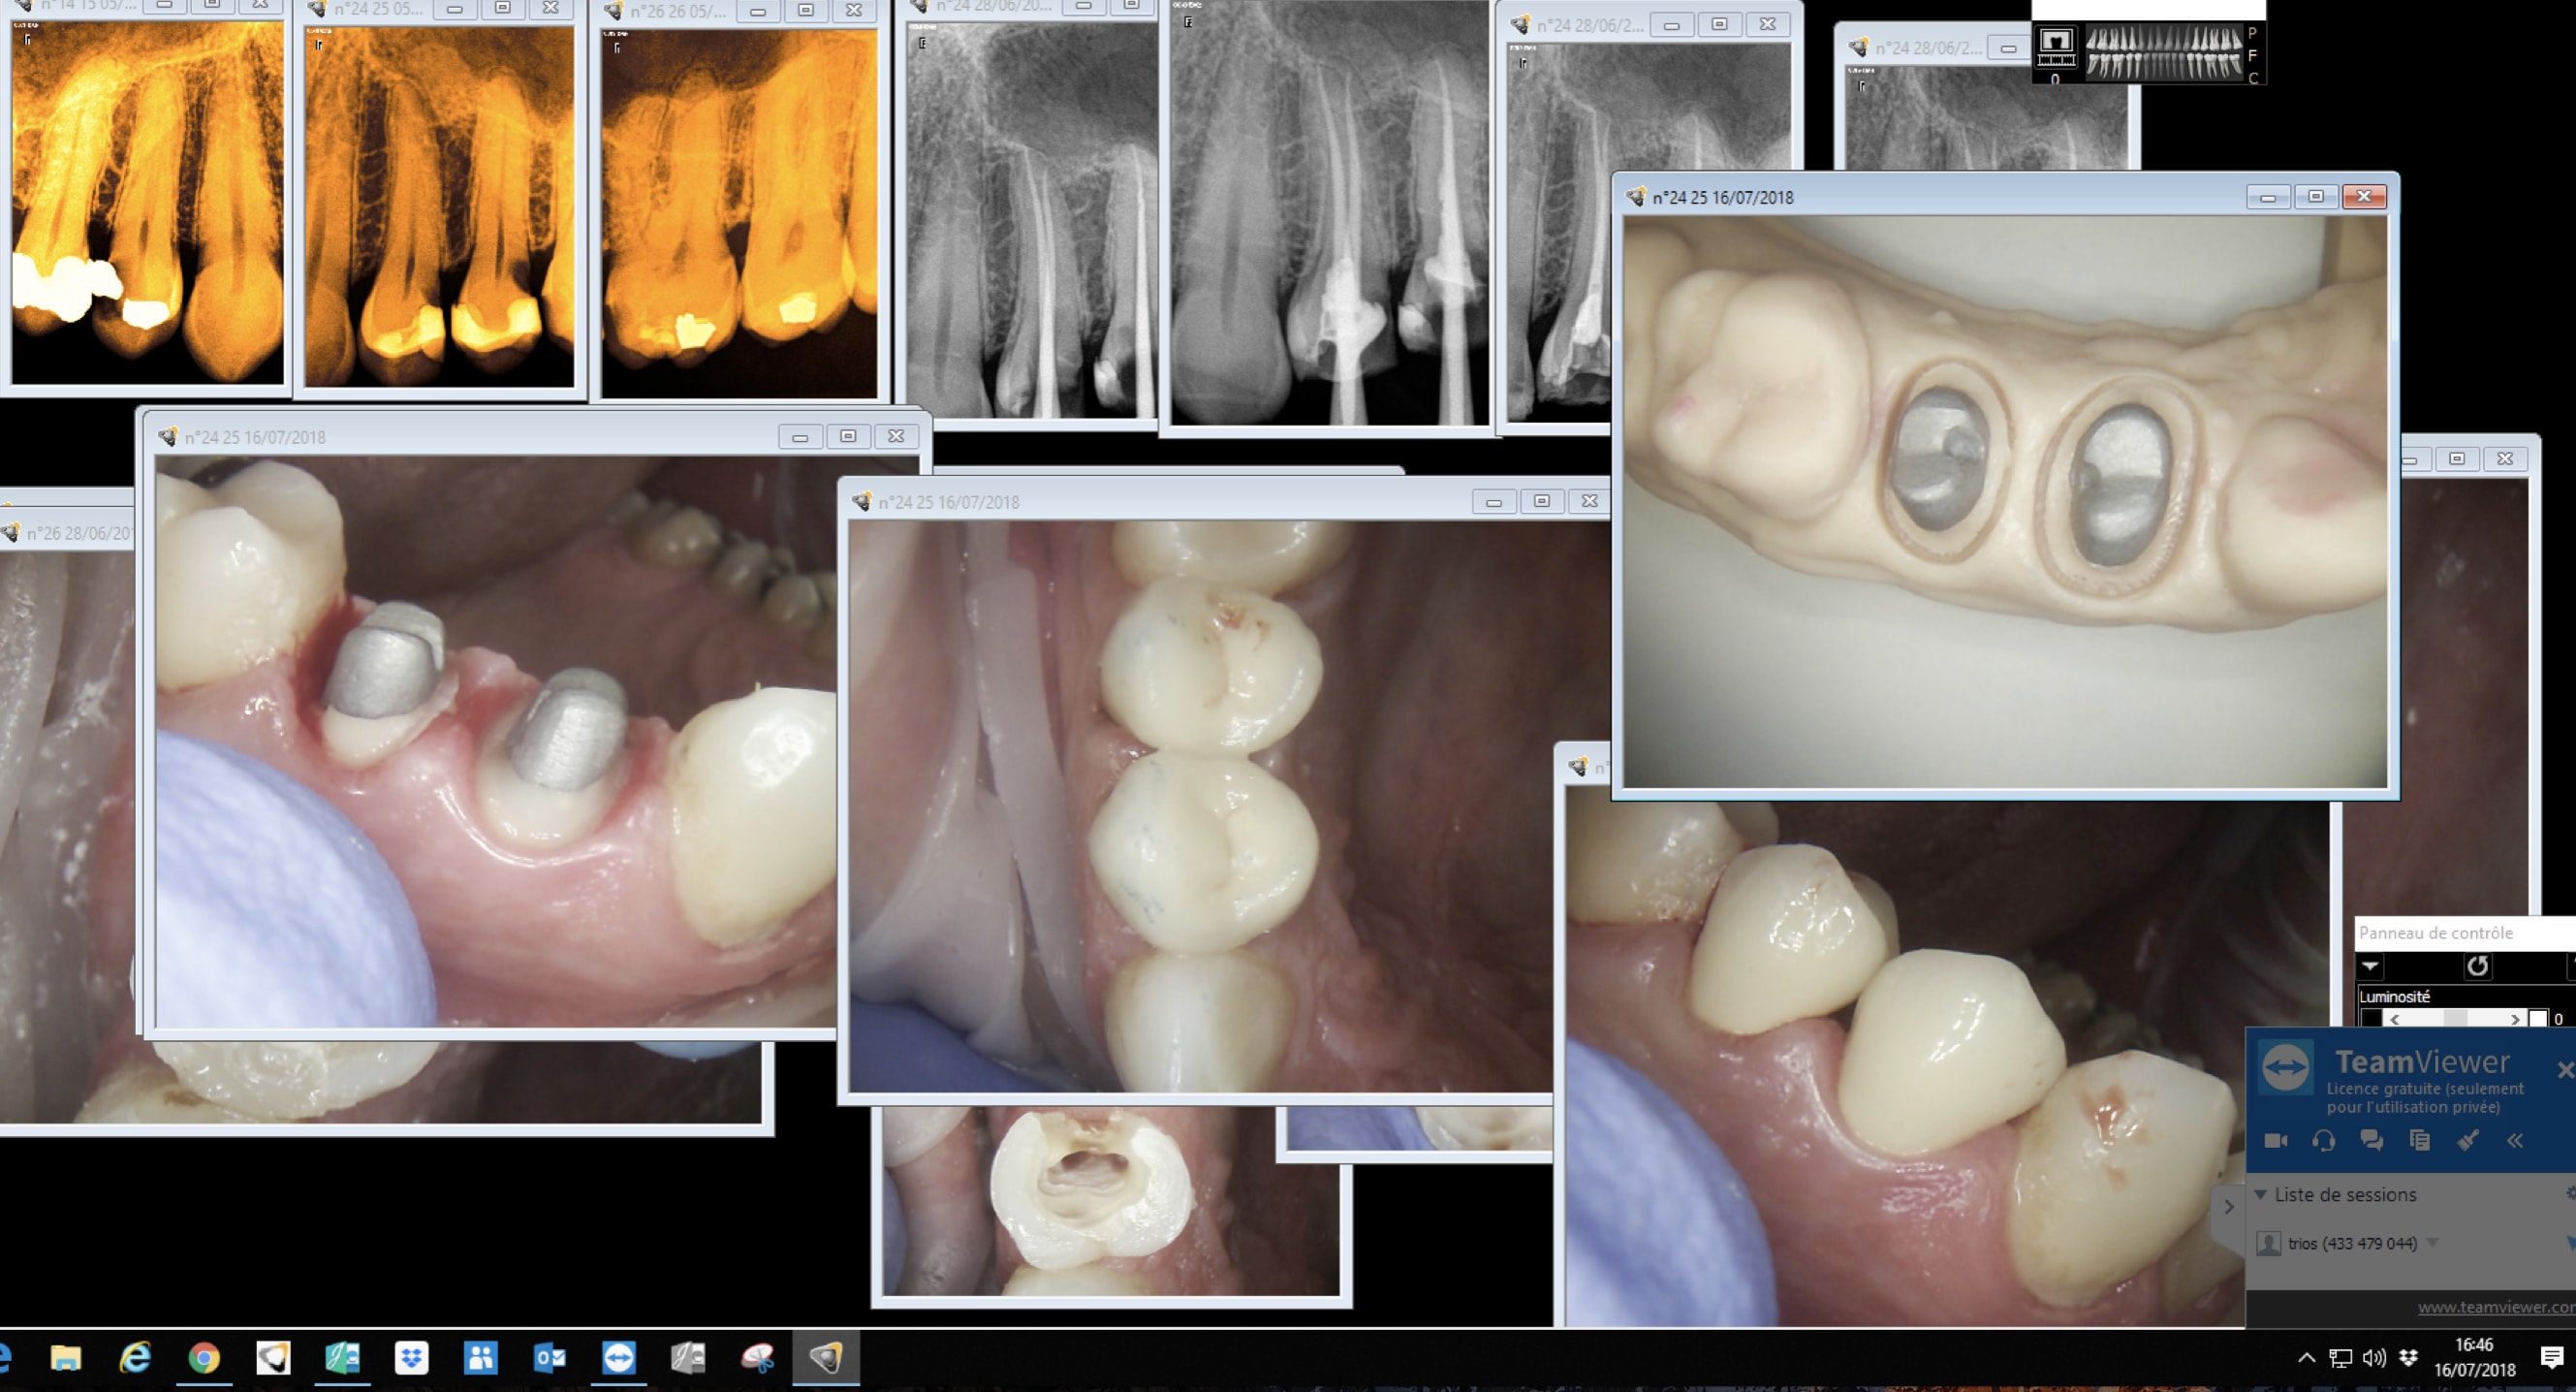

Bon sur ce coup j'ai joué du laser.